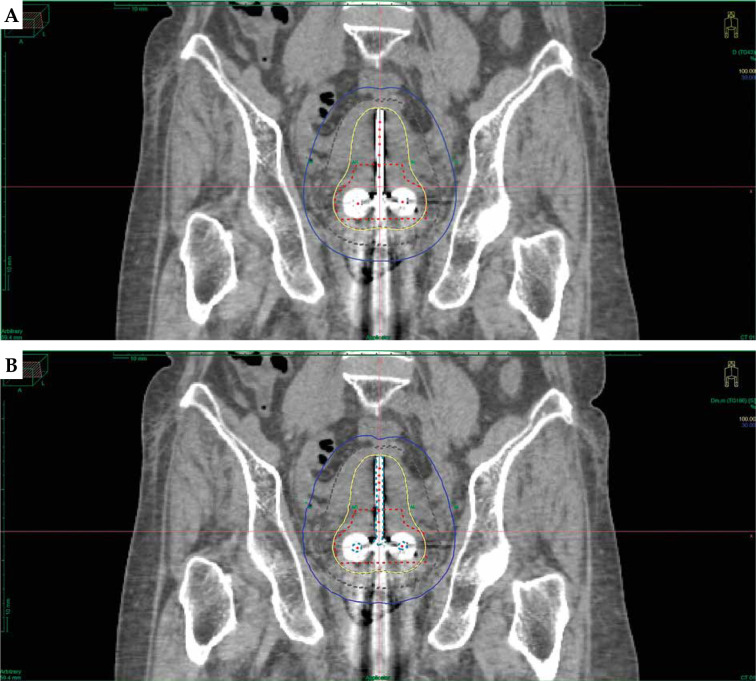

Purpose: The present study evaluated the dosimetric impact and compared the dose variations between the advanced collapsed cone engine (Task Group 186) and Task Group 43 plans for cervical cancer using tandem and ovoid applicators.

Material and methods: Thirty cervical cancer patients underwent iridium-192 (192Ir) high-dose-rate (HDR) intra-cavitary brachytherapy using tandem and ovoid applicator. Original treatment plans for all patients were created using TG-43 dose calculation formalism. Subsequently, these plans were re-calculated using ACE (TG-186) algorithm and were not re-optimized, so that dwell time and dwell positions were identical in both plans. High-risk clinical target volume and organs at risk were contoured in each dataset. Significant air gaps within region of interest and use of high density applicator materials were also considered. The assessment encompassed a point-based evaluation, extraction of dosimetric parameters from dose-volume histogram (DVH), and plan evaluation indices for each algorithm.